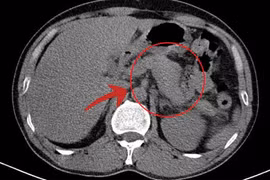

Sỏi đường mật nếu không được phát hiện sớm và điều trị kịp thời có thể gây ra nhiều biến chứng nguy hiểm như viêm đường mật, viêm tuỵ, xơ gan…Ngoài ra, sỏi đường mật trong gan là yếu tố nguy cơ gây ung thư đường mật trong gan.

(khoahocdoisong.vn) - Sỏi đường mật trong gan (thường được gọi tắt là sỏi gan), bản chất là sỏi mật nhưng nằm trong các ống gan. Sỏi trong gan thường dễ gây biến chứng hơn so với sỏi tại các vị trí khác trong đường mật.